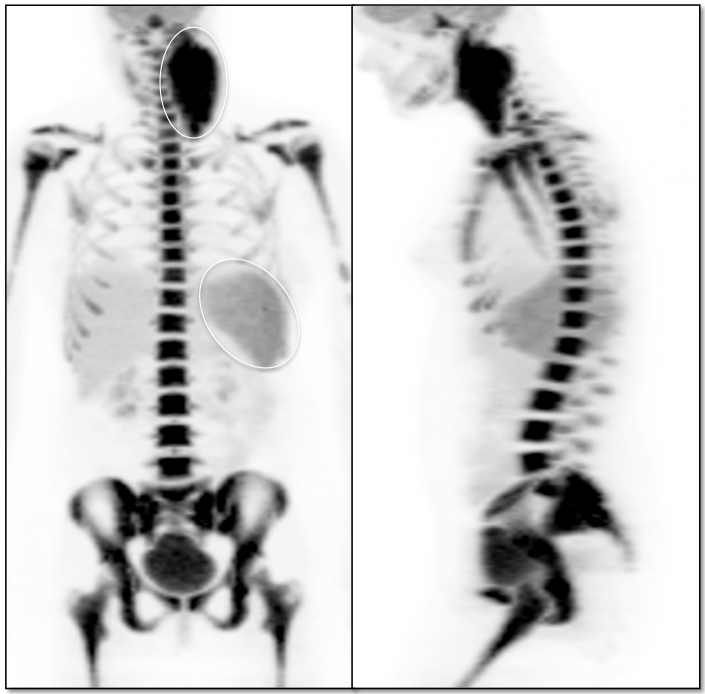

Normal Skeletal Uptake

Mild to moderate FDG uptake can be normally seen within red marrow, most commonly affecting the vertebral bodies, sternum, pelvis, and proximal long bones (it is not unusual to see fairly prominent uptake within the proximal half of the femurs). This red marrow uptake can be quite heterogeneous at times, yet still normal.

Diffuse Skeletal Uptake:

Intense and diffuse reactive marrow uptake is frequently seen as the result of chemotherapy and/or colony stimulating factors (discussed in detail, here).

If rather diffuse and intense uptake is noted without a history of recent chemotherapy or colony stimulating factors, be suspicious of infiltrating disease such as lymphoma.

Focal Skeletal Uptake:

Focal skeletal uptake warrants extremely close assessment of the co-registered CT images to exclude malignancy. Other etiologies of focal skeletal uptake include fracture, arthropathy, infection and several benign bone lesions.